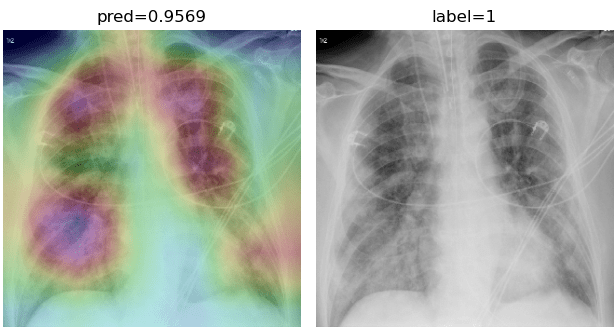

Appendix B More Grad-CAMs of the COVID-CXNet Model with Lung Segmentation Preprocessing

Figure 21: Grad-CAMs from COVID-CXNet with lung segmentation module